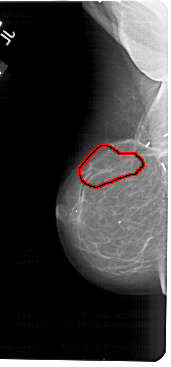

FILE: A_1613_1.LEFT_MLO.OVERLAY

TOTAL_ABNORMALITIES 1

ABNORMALITY 1

LESION_TYPE CALCIFICATION TYPE PLEOMORPHIC DISTRIBUTION LINEAR

ASSESSMENT 5

SUBTLETY 4

PATHOLOGY MALIGNANT

TOTAL_OUTLINES 1

BOUNDARY